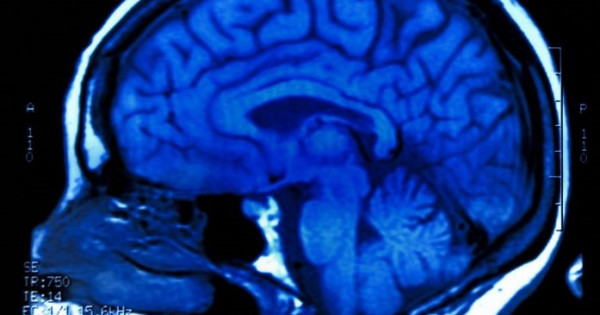

عالىمدار ادام ميىنىڭ قۇرى­لىمىنا قاتىستى تاڭعالارلىق جاڭالىق اشىپ, بۇرىن بەل­گىسىز بولىپ كەلگەن جۇقا قاباتتى انىق­تادى.

بۇل قابات ميدىڭ سىرتقى قىرتىسى مەن ىشكى قۇرىلىمدارى اراسىندا ورنا­لاسقان جانە ونىڭ نەيروندىق بايلانىس­تاردى رەتتەۋگە قاتىساتىنى بايقالعان. زەرتتەۋشىلەر بۇل جاڭالىقتىڭ التسگەيمەر, پاركينسون سياقتى نەۆرولوگيا­­لىق ­اۋرۋلاردى ەمدەۋدە جاڭا مۇمكىندىك ­تۋ­عىزۋى عاجاپ ەمەس.